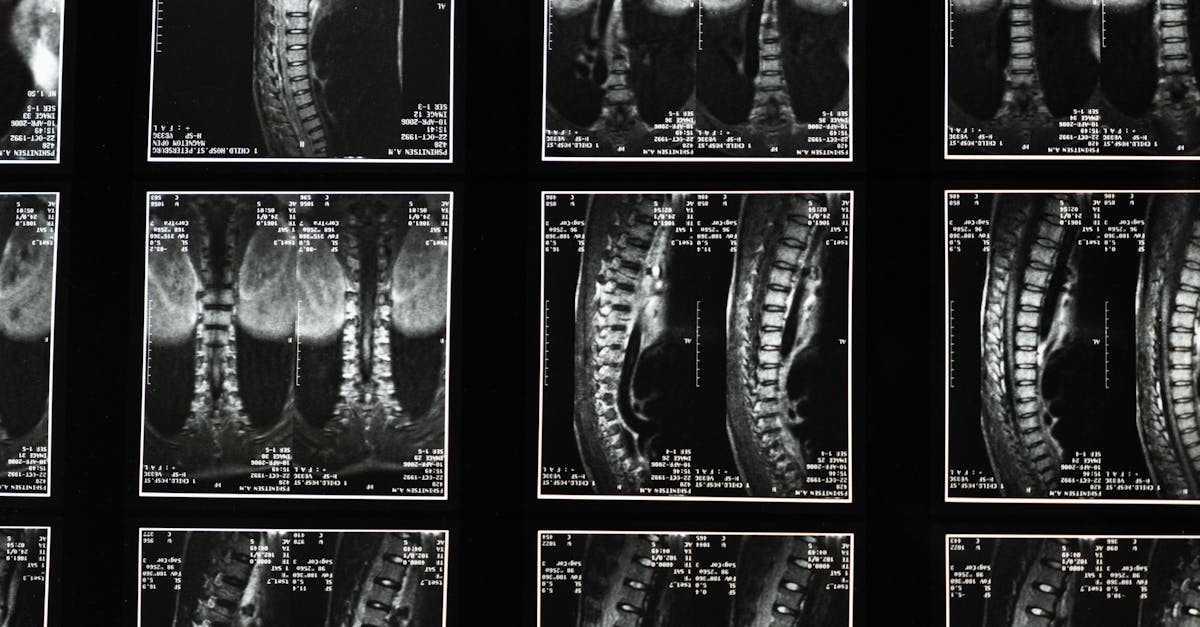

Pour intégrer efficacement la décompression neurovertébrale dans un programme de rééducation, plusieurs étapes clés doivent être suivies. Tout d’abord, une évaluation initiale est primordiale. Cette phase comprend l’analyse des antécédents médicaux du patient et la réalisation d’examens d’imagerie comme une IRM pour cerner l’état de la colonne vertébrale.

La première étape pour procéder à la décompression neurovertébrale consiste en une évaluation initiale. Cette phase est cruciale pour déterminer la gravité des symptômes et comprendre les besoins spécifiques de chaque patient. Un praticien de santé compétent procédera à un examen physique détaillé, tout en prenant en compte l’historique médical et en réalisant des examens d’imagerie (IRM ou radiographies) pour établir un diagnostic précis.

La première étape du processus est l’évaluation initiale. Cette phase consiste à effectuer un examen approfondi des antécédents médicaux du patient, incluant une discussion sur la nature des douleurs ressenties. Il est également fondamental de réaliser des examens d’imagerie tels que des IRM ou des radiographies, pour évaluer l’état de la colonne vertébrale et identifier les zones spécifiques nécessitant un traitement. Cette évaluation permet de définir les axes de travail pour le traitement de décompression neurovertébrale.